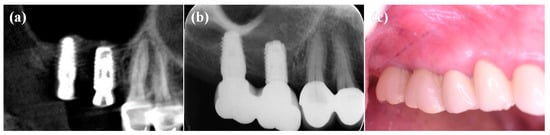

Similar findings were also observed in other patients with the IDCT-modified Ti implant treatment. The follow-up after four months showed a radiologically and clinically health condition reflected by no further bone loss found around the dental implant (Figure 7 and Figure 8).

Figure 7.

The radiographic images taken from the right maxillary molar with the IDCT-modified Ti implant after (a) immediate placement, (b) four months placement, and (c) clinical evaluation (four months placement).